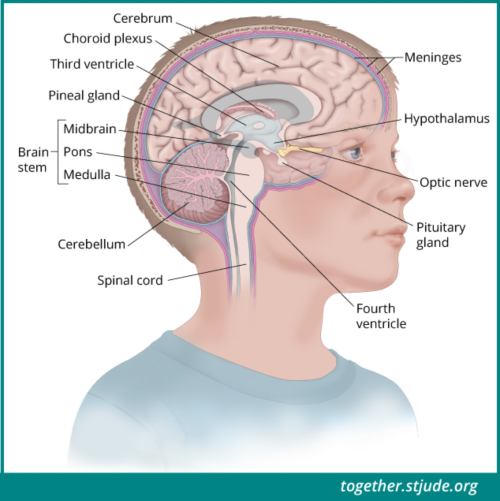

संग्रह 2021: बच्चों के लिए मस्तिष्क चित्र

यहां आपको वह मिलेगा जिसकी आपको तलाश थी - बच्चों के लिए मस्तिष्क चित्र